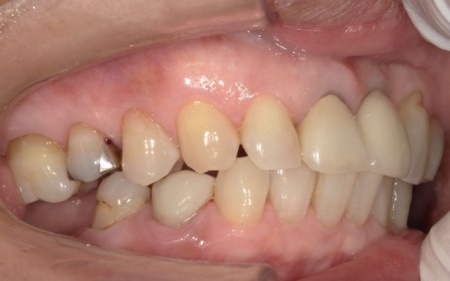

インプラントが顎の骨と結合したあと、人工歯を装着します。

また、手前の歯にも新しい被せ物を装着しました。

最後に、見た目や噛み合わせに問題がないことを確認し、治療を終了しています。